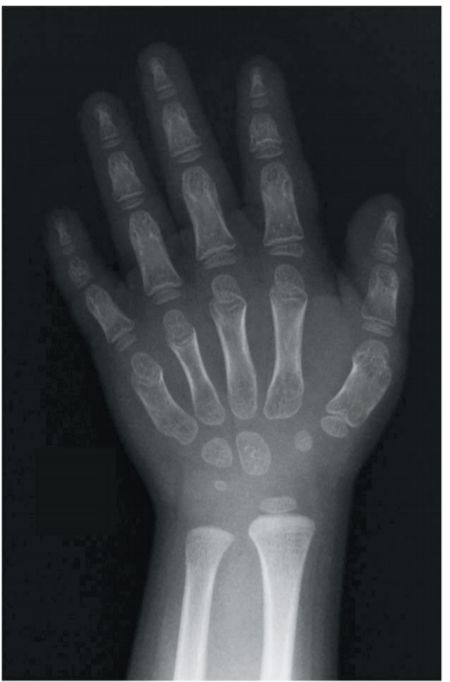

51 歳の男児。背が低いことを心配した母親に伴われて来院した。幼稚園では他の 児に比べて少し背が低い程度であったが、最近、小学校の同級生との身長差が徐々 に拡大してきているという。在胎 38 週、体重 2,780 g、骨盤位で出生した。母子 健康手帳によると、出生時身長 49.0 cm、Apgar スコア点(分)であった。小 学校の成績は普通で、家族歴に特記すべきことはない。意識は清明。活気はある。 身長 106.3 cm(安2.6 SD)、体重 21.0 kg(安0.5 SD)。外表奇形や四肢短縮を認め ない。血液生化学所見:TSH 1.1 μU/ml(基準 0.44〜4.1)、FT3 3.0 pg/ml(基準 2.5〜4.5)、FT4 1.2 ng/dl(基準 0.8〜2.2)。手エックス線写真(別冊No. 4)を別に 示す。 現時点の対応で適切なのはどれか。 (A) 染色体検査を行う。 (B) 心配ないと説明する。 (C) 年後の再診を指示する。 (D) アルギニン負荷試験を行う。 (E)血中ビタミン D 濃度を測定する。